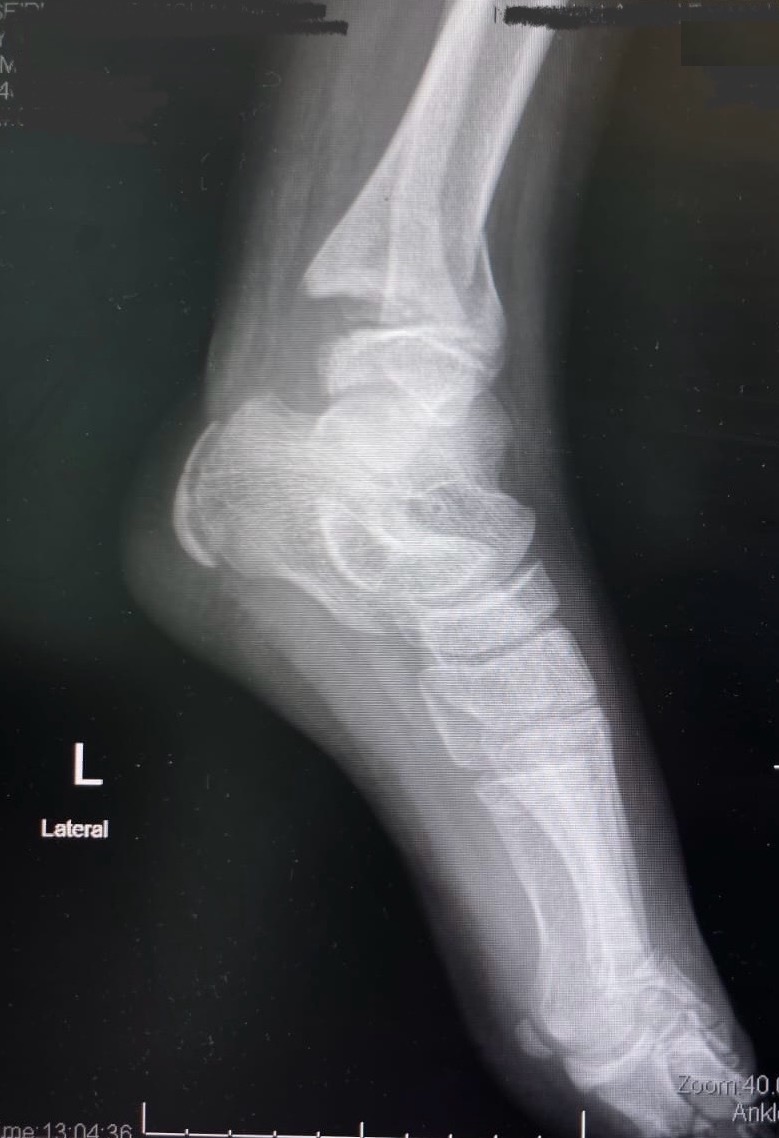

• Medical records of patients with documented FCS from May 2007 to January 2009 were retrospectively reviewed. Consecutive, matched control patients were identified based on similar hindfoot, mid-foot and/or forefoot injuries who did not undergo foot fasciotomy during the same period. The primary outcomes analysed were the development of claw or hammer toes and neuropathic pain.

• 19 patients with foot fasctiotomies were identified and matched with 19 controls. Median follow-up was 19.5 months (range, 3.5-47.5 months) for the combined cohorts. The most common mechanism of injury was an explosive blast. Nine fasciotomy and nine control patients sustained open foot fractures. Significantly more patients with foot fasciotomies developed claw toes (50% vs 17%, p=0.03). There were no significant differences in the development of neuropathic pain, sensory deficits, motor deficits, chronic pain, stiffness or infection. The fasciotomy patients underwent an average of 5.5 surgeries per patient versus 4 surgeries per patient in the control group.